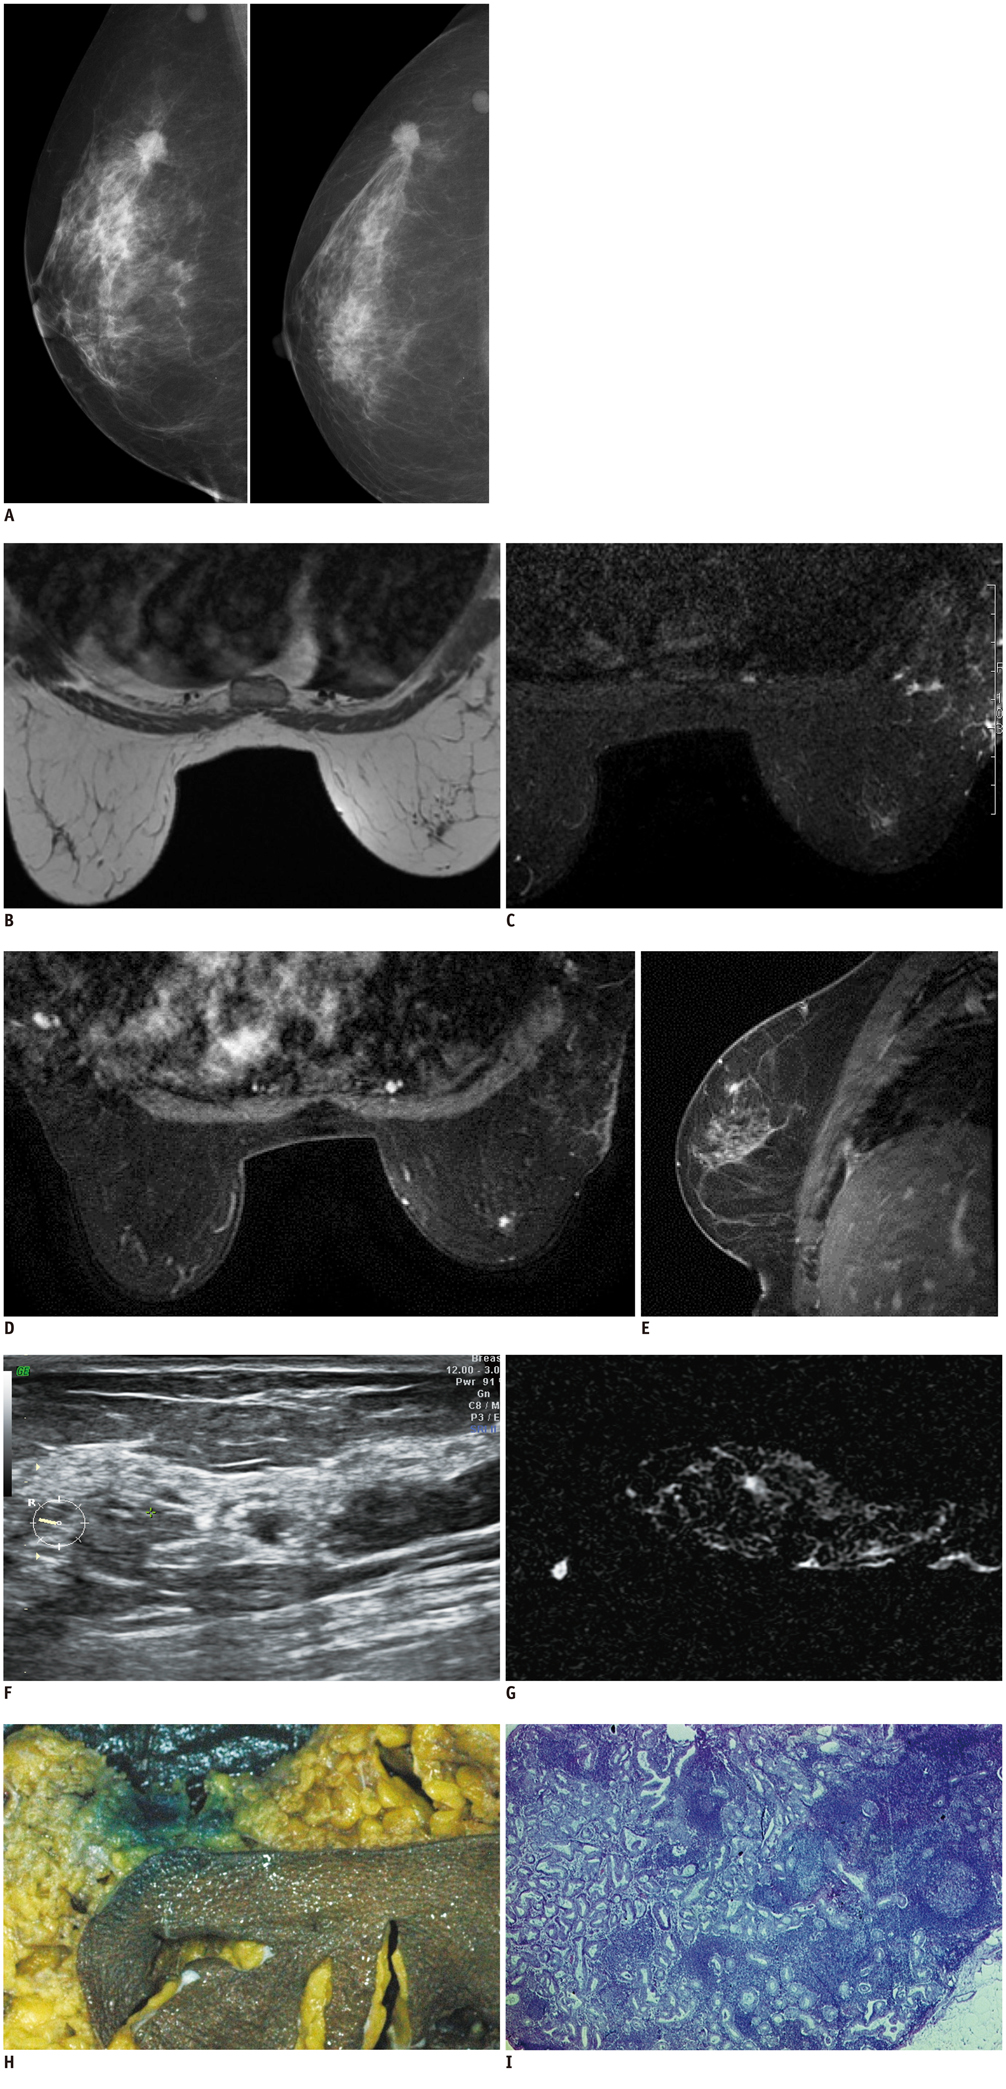

Diagnosis of a Malignant Intramammary Node Retrospectively Aided by Mastectomy Specimen MRI-Is the Search Worth It? A Case Report and Review of Current Literature

- Metastases to intramammary nodes have been shown to be an independent predictor of poor outcome in patients with breast cancer, such as axillary lymph node metastases. The detection and accurate characterization of these nodes preoperatively is thus crucial for the staging and planning of treatment for breast carcinoma, particularly in cases with axillary lymph node negative disease as it upgrades the disease staging. We herein report the first case where we detected an intra-mammary node on specimen MRI after the primary pathological gross specimen evaluation failed to detect the node.